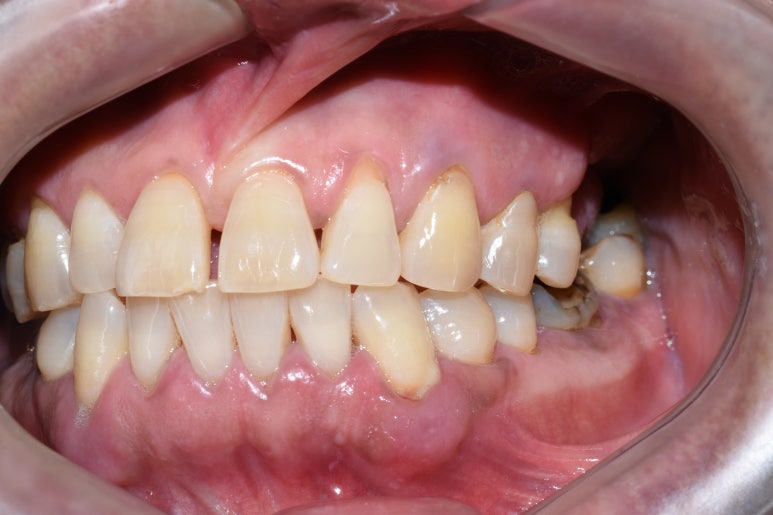

오랜 시간 치아가 방치되어 아래 파노라마와 같은 모습이었습니다.

큰 위쪽 어금니는 3개가 없고 하나는 매우 흔들리는 상태,

아래쪽 큰 어금니는 파절되고 썩어있는 상태였습니다.

↑치료 전 사진입니다. 큰 어금니 쪽에 치아들이 성하지 않아

씹기가 힘든 상태입니다.